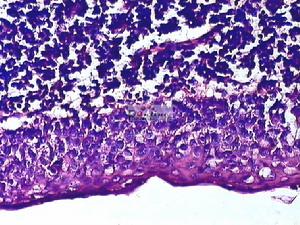

2.病理學檢查 當非侵犯性診斷方法均不能診斷時, 最後可考慮經玻璃體作細針穿刺取得脈絡膜標本做活檢及免疫組化以求確診, 瘤栓隨血流駐留在脈絡膜中, 小血管層,脈絡膜因腫瘤浸潤而增厚。腫瘤不穿破玻璃膜;視網膜神經上皮可脫離,但很少與脈絡膜發生粘連, 因而錐, 桿體細胞受損少, 脈絡膜轉移癌的細胞形態、結構和排列保留了原發癌的特點。原發於乳腺癌者,癌細胞常呈腺樣排列或形成上皮巢;肺或支氣管腺癌常為腺樣或不規則細胞條索;肺燕麥細胞癌的瘤細胞體積較小,呈巢狀排列 無腺泡樣結構;原發於胃和甲狀腺者呈局灶性隆起生長;來自皮膚的黑色素瘤一般均含有較多的黑色素, 細胞分化好者,常保持原發腫瘤的組織模式。分化差者,組織學檢查常無法了解其原發腫瘤的特性, 需經特殊染色, 電鏡, 免疫組織化學或檢測血中癌胚抗原等做進一步鑑別。